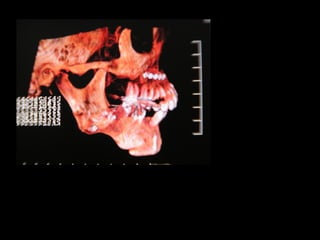

Cóndilo

Apófisis estiloides

Apófisis pterigoides

Vómer

Apófisis basilar

Foramen magnum